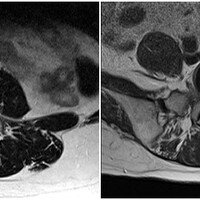

내게 맞는 수술 재활치료가 성패 가른다

일흔다섯 살 김 할머니는 요즘 하루하루가 즐겁다. 지난 10여 년간 그녀의 외출과 여행을 막아온 퇴행성관절염을 인공관절 수술로 치료했기 때문이다. 수술에 대한 부담감은 있었지만 6개월~1년씩 무릎 통증을 줄여준 연골주사가 채 1주일…